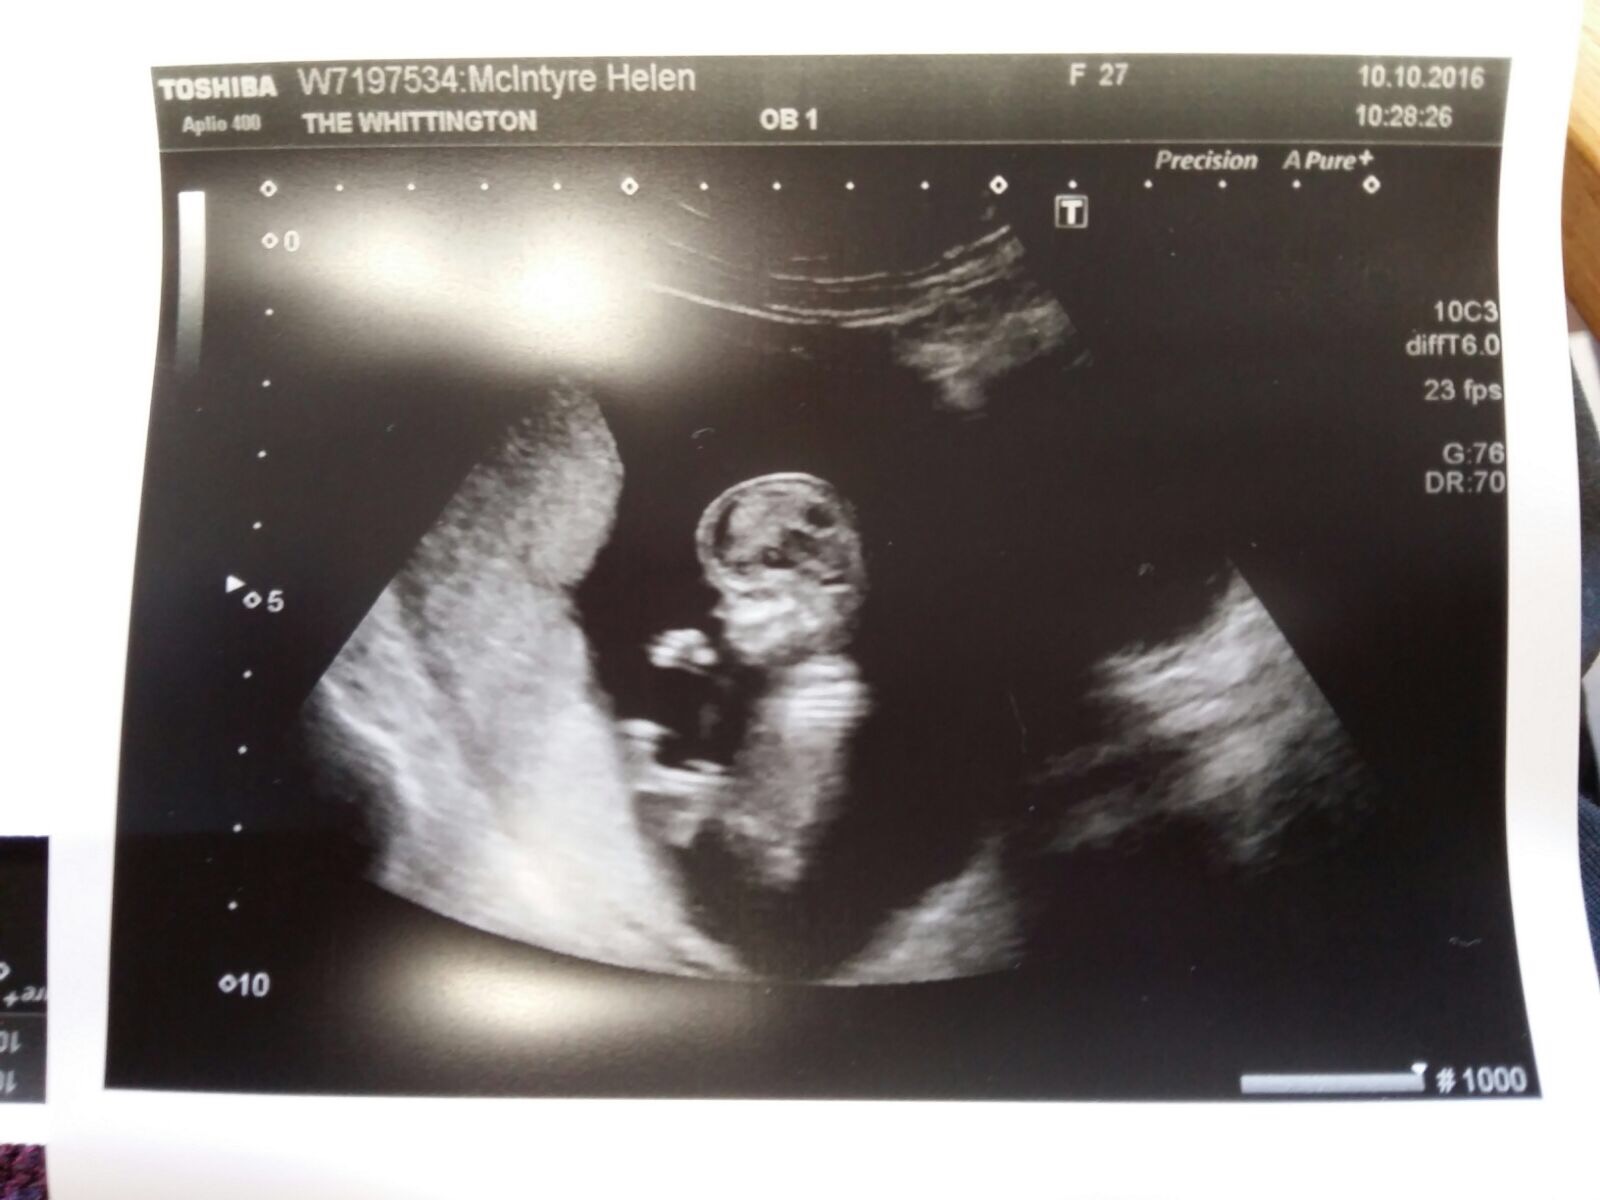

I got this image to play with- first grandchild.

Now the “moon” is full, and perfect, unlike the corroded and degenerated forms I was making earlier, which reflected my mother’s condition. It’s outsize, like a real foetus. The use of a sieve is playful, making fun of the idea of a brain being “like a sieve”, but also reminds of my mother at the other end of the spectrum. The use of cutlery is meant to be playful, although a sense of threat might be felt too, but the pose is of a young child exploring- crawling. The “technique/ technology” involves blocking light to form an image, and the ultrasound works in a similar way but with sound waves. Both are testament to something “being there”, to presence. Both create positives out of negatives. Overall, it should be fun, joyful, new- positive in that sense too.